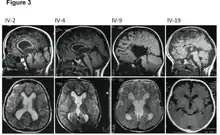

![]() | |

| MRI images showing megalencephaly in four family members who all have unusually large skulls (the family is affected by an autosomal recessive syndrome caused by a KIF7 mutation that induces multiple epiphyseal dysplasia)[1] | |